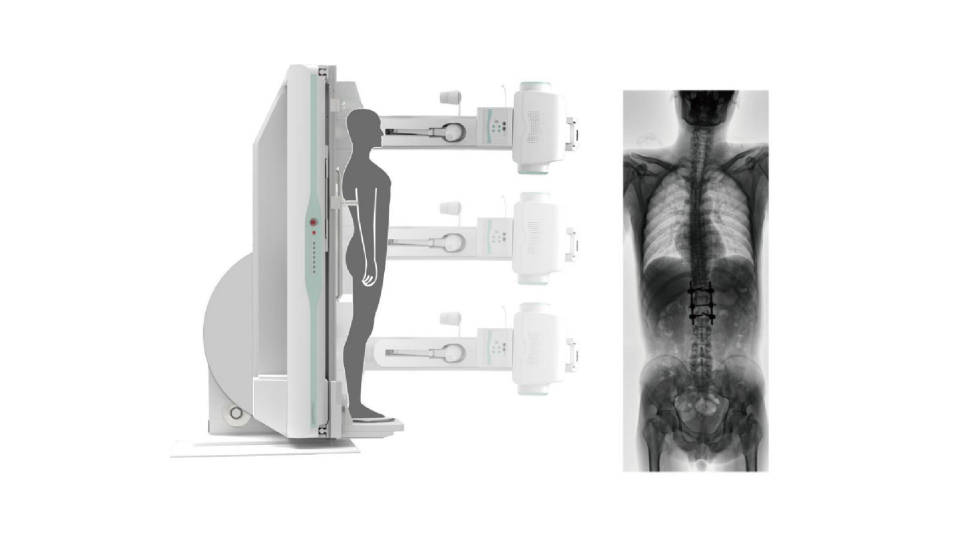

●呈现全下肢或全脊柱图像

●在脊柱及下肢畸形矫正手术治疗中,为术前方案制定和术后复查提供精准测量

●有效解决传统X光片不能一次成像问题,为患者提供更加优质的医疗服务

点片装置可实现大范围纵向移动,高效完成各部位、全身拼接等检查需求